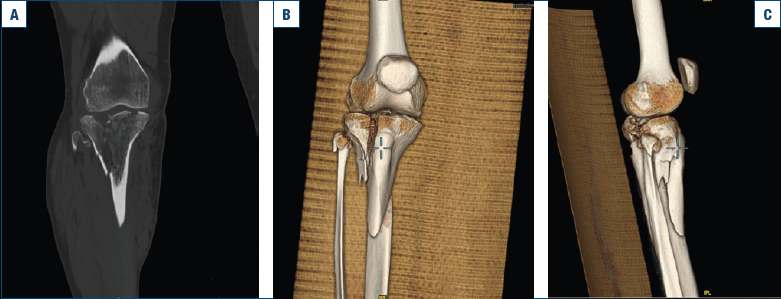

Uomo di 58 anni, caucasico, diabetico, ex fumatore (20 pack-year tra i 20 e i 40 anni). Anamnesi negativa per osteoporosi diagnosticata o trattamento pregresso con bisfosfonati. Affetto da sindrome ansioso-depressiva in trattamento farmacologico da 3 anni. Il paziente è stato coinvolto in un incidente stradale con trauma diretto all’arto inferiore destro, riportando una frattura pluriframmentaria bicondilare del piatto tibiale con coinvolgimento metadiafisario (Tipo VI secondo la Classificazione di Schatzker), documentata tramite TC e ricostruzione 3D (Fig. 1a, b).

Figura 1. (a, b, c) TC e ricostruzione 3D tramite Tc della frattura del piatto tibiale.